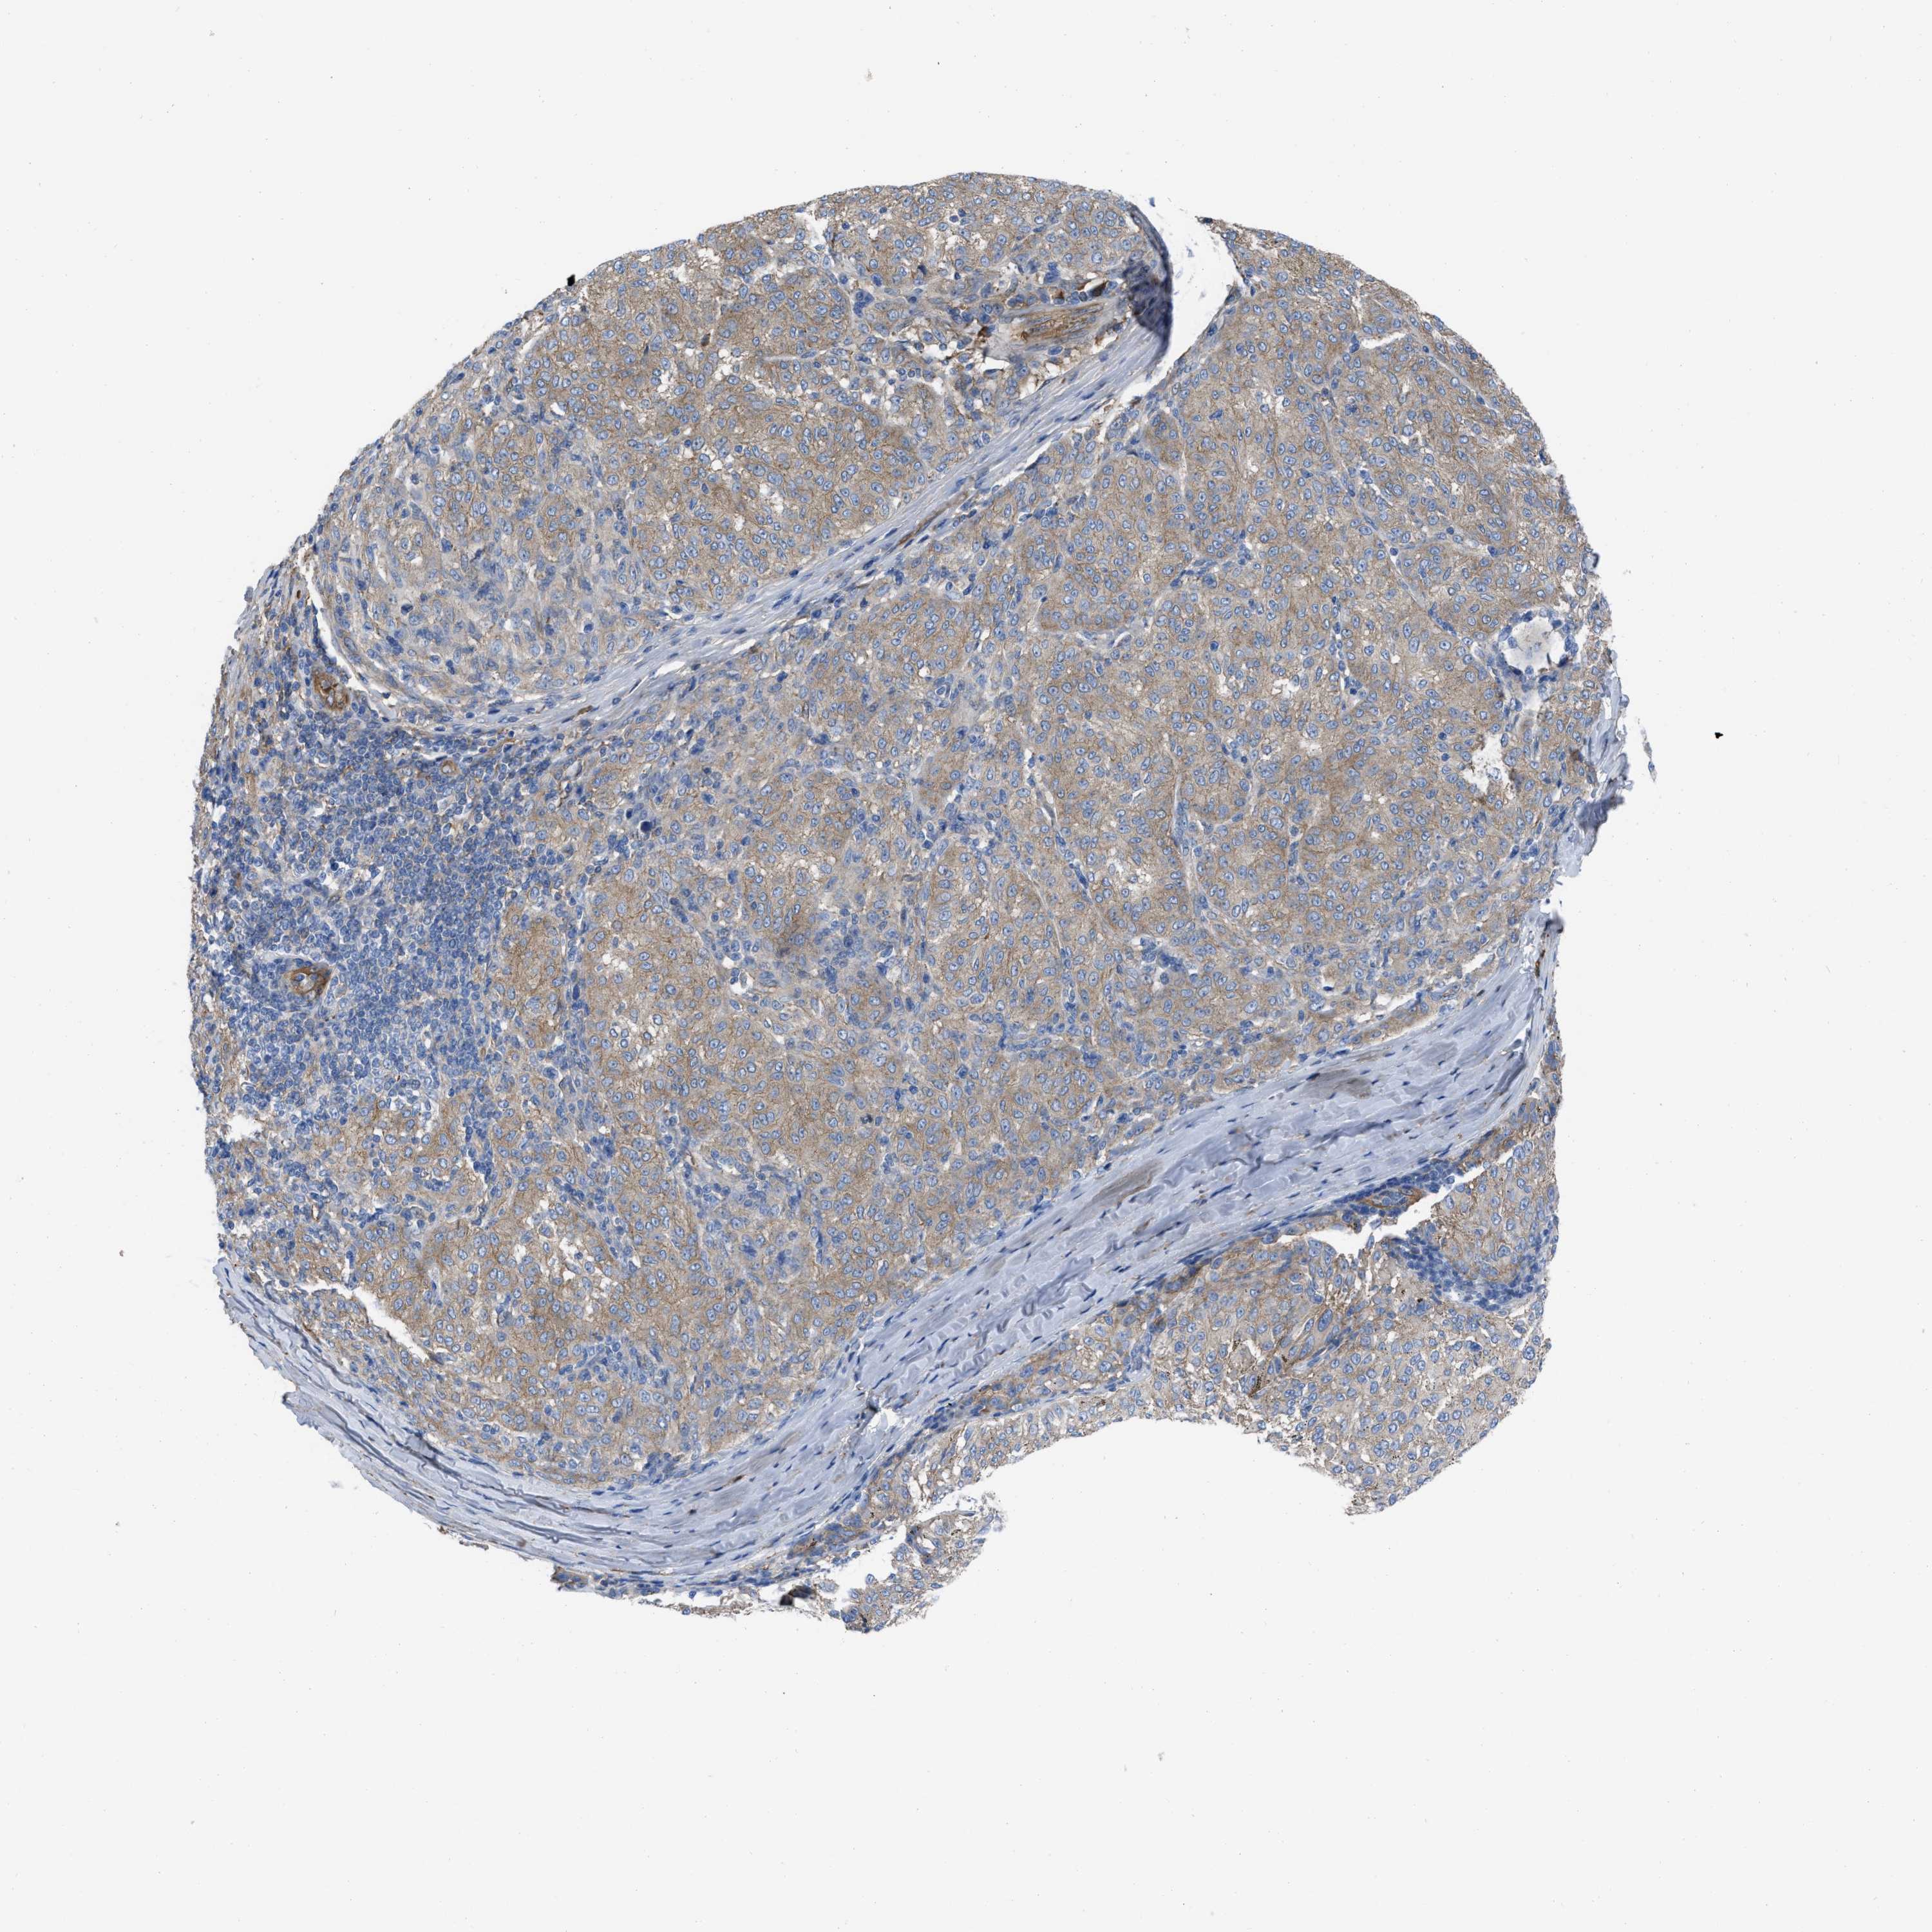

MELANOMA - Protein expressioni

A mouse-over function shows sample information and annotation data. Click on an image to view it in a full screen mode. Samples can be filtered based on level of antibody staining by selecting one or several of the following categories: high, medium, low and not detected. The assay and annotation is described here.

Note that samples used for immunohistochemistry by the Human Protein Atlas do not correspond to samples in the TCGA dataset.

Antibody stainingi

Antibody staining in the annotated cell types in the current human tissue is reported as not detected, low, medium, or high, based on conventional immunohistochemistry profiling in selected tissues. This score is based on the combination of the staining intensity and fraction of stained cells.

Each image is clickable and will lead to virtual microscopy that enables deeper exploration of all samples and also displays staining intensity scores, fraction scores and subcellular localization as well as patient and tissue information for each sample.

Antibody HPA003747

Antibody HPA019769

Malignant melanoma, NOS

Malignant melanoma, Metastatic site